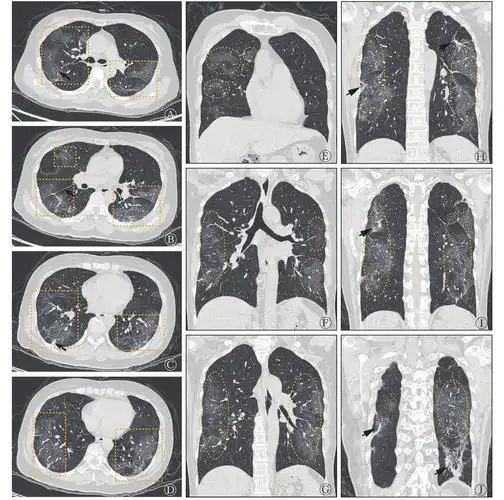

图 1 新型冠状病毒肺炎患者(女性,52岁)发病第8天的胸部ct肺